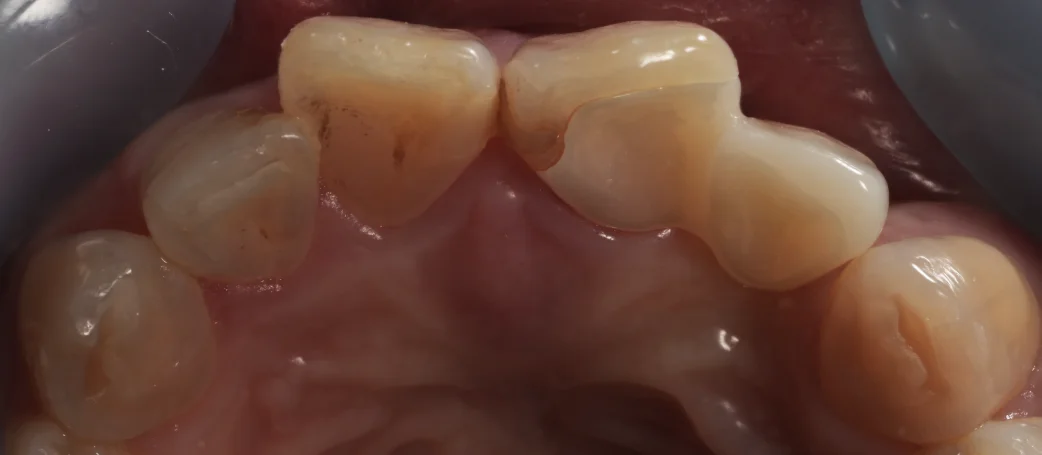

最終的なものを入れた状態の写真がこちらです。

こんな感じで、一層削った部分だけを覆って、横に伸ばしているんですね。

写真上だと少し隙間があるように見えるかもしれませんが、仮に合わせた状態でちょっと浮いているだけで、実際には隙間がなく非常にいい適合を得られていました。

噛む面からの術前術後です。